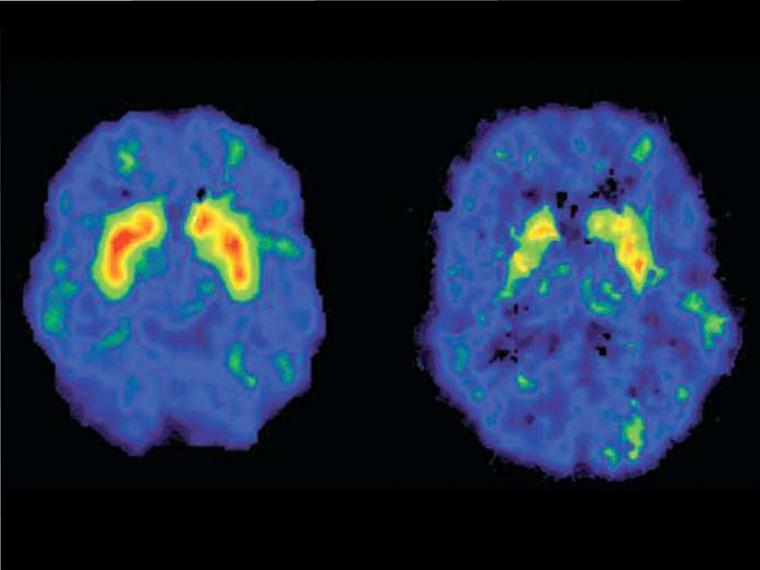

La metanfetamina aumenta la cantidad de dopamina en el cerebro, una sustancia química natural que participa en el movimiento corporal, la motivación y el refuerzo de las conductas que producen satisfacción. La capacidad de la droga de elevar con rapidez el nivel de dopamina en las áreas de recompensa del cerebro refuerza grandemente el comportamiento de consumir la droga y hace que la persona quiera repetir la experiencia.

- cambios en la estructura y el funcionamiento del cerebro